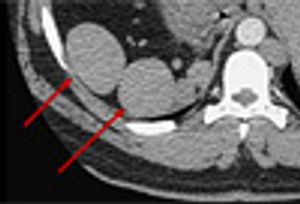

A 38-year-old man with a history of alcoholism, intravenous drug use, and cerebrovascular accident was referred for assessment of possible endocarditis, based on history, fever 39 °C (102.9 °F) and mildly elevated troponin level.